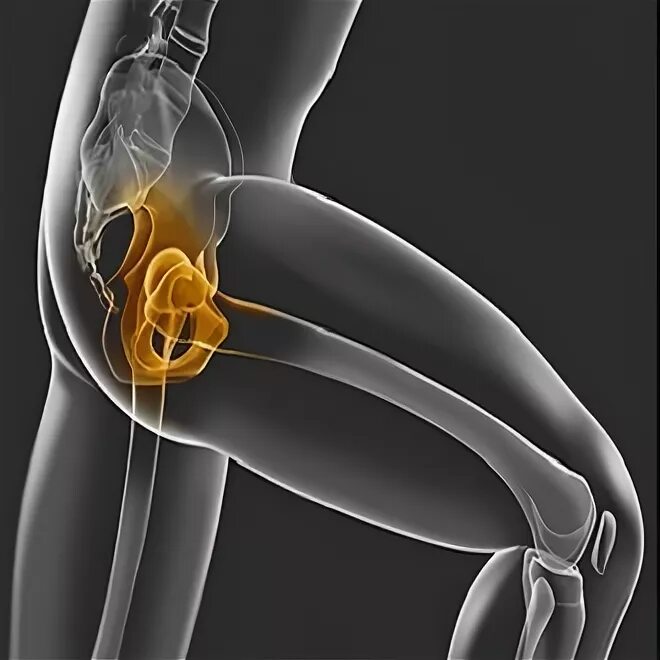

Как лечить синовит тазобедренного сустава